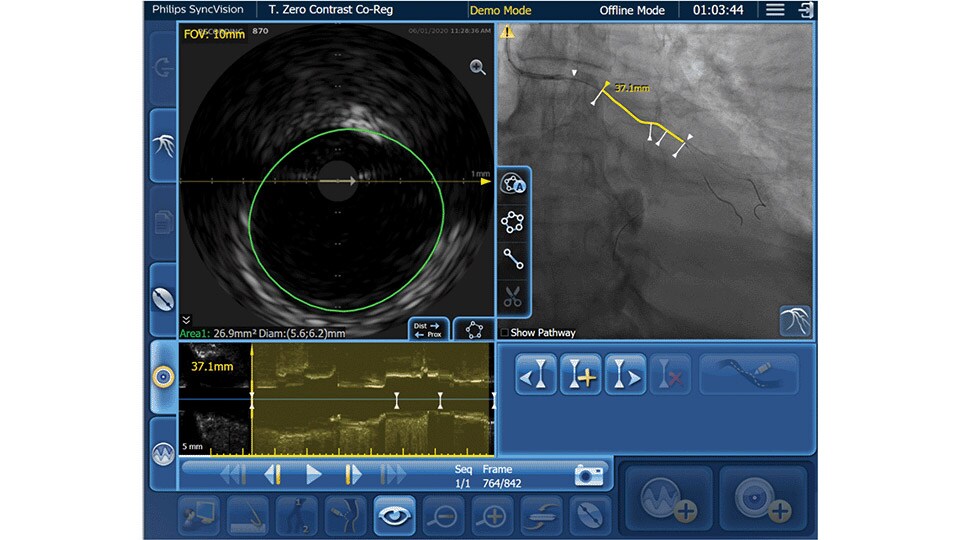

Only Philips instant-wave free radio (iFR) has co-registration for advanced physiologic guidance, allowing you to precisely determine lesion location and severity.

As an alternative or adjunct to IVUS Co-registration, iFR pullback can be co-registered onto the angiogram to assess both the degree and length of vessel stenosis.